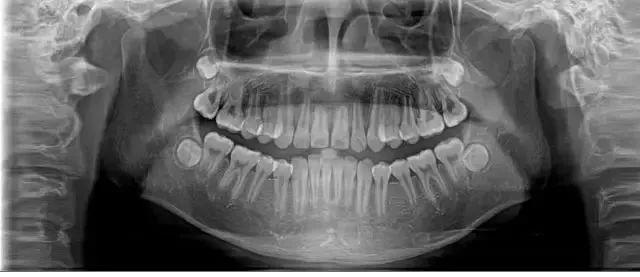

日前, 25歲的李女士因?yàn)檠例X松動(dòng)、牙齦出血前來(lái)鄭州大學(xué)第一附屬醫(yī)院河南省口腔醫(yī)院就診。

醫(yī)生經(jīng)過(guò)系統(tǒng)檢查后,確定這位年輕人出現(xiàn)全口多處牙齒的松動(dòng),診斷為侵襲性牙周炎。

經(jīng)過(guò)口腔醫(yī)院診斷,她患上了嚴(yán)重的牙周炎,醫(yī)生先后為其拔除了11顆牙齒,并種植了10顆牙齒。

28歲的小孟因刷牙時(shí)突然一顆門牙脫落,當(dāng)她到醫(yī)院就診時(shí),醫(yī)生告訴她上排牙已全部不能保留。

小孟的牙齒已經(jīng)出現(xiàn)了不同程度的松動(dòng),而導(dǎo)致她松動(dòng)至功能喪失的是嚴(yán)重的牙周炎。終只能將其牙拔去后,花費(fèi)十五六萬(wàn)元選擇種植牙。